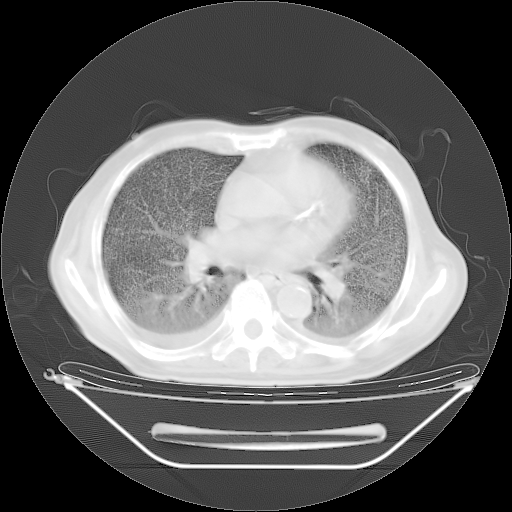

今天复查肺部CT,发现双肺广泛磨玻璃样改变。所以我把3月19日和5月9日相隔50天的肺部CT上传。请大家会诊。

2009年3月19日肺部CT片。

2009年3月19日肺部CT